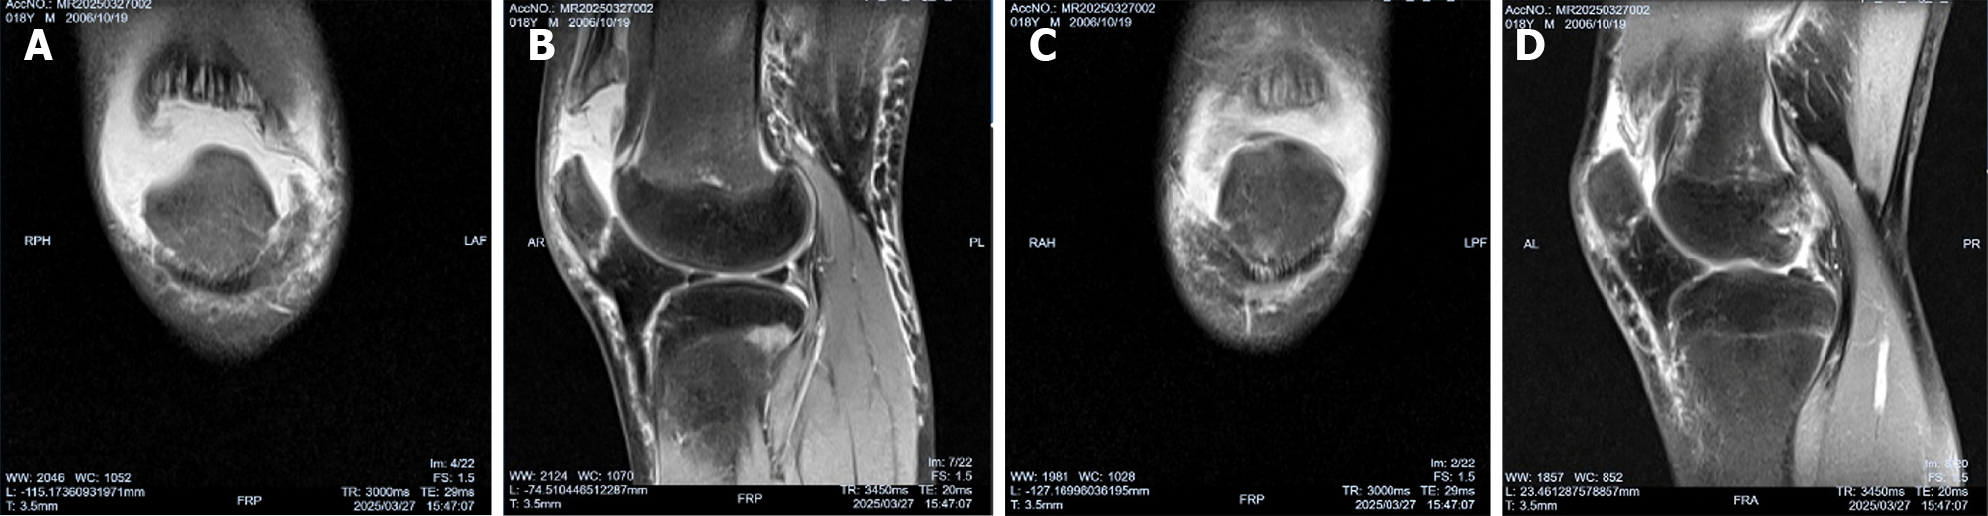

Figure 2 Preoperative magnetic resonance imaging showed the bilateral sleeve fracture of the superior pole of the patella.

A: Coronary magnetic resonance imaging (MRI) in the right knee; B: Sagittal MRI in the right knee; C: Coronary MRI in the left knee; D: Sagittal MRI in the left knee.